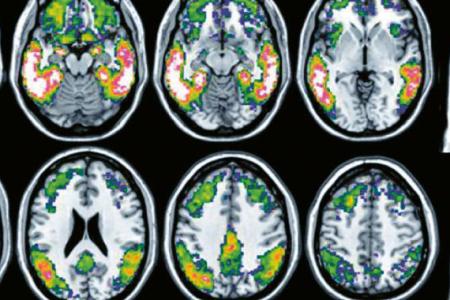

La maladie d’Alzheimer, l’une des maladies neurodégénératives les plus fréquentes, entraîne une perte progressive de la mémoire et de l’autonomie. Elle est caractérisée par l’accumulation dans le cerveau de protéines neurotoxiques, la plaque amyloïde et la protéine tau. Évoluant à bas bruit pendant des décennies, son diagnostic très précoce est essentiel afin d’intervenir le plus tôt possible dans le processus pathologique.

Une équipe de l’Université de Genève et des HUG a démontré que le PET tau – une technique d’imagerie très récente permettant de visualiser la protéine tau – est capable de prédire le déclin cognitif des personnes mieux que les techniques d’imagerie habituellement utilisées. Ces résultats, à lire dans la revue Alzheimer’s & Dementia : The Journal of the Alzheimer’s Association, plaident pour l’introduction rapide de cet examen dans la routine clinique afin d’apporter aux malades des solutions précoces et individualisées.